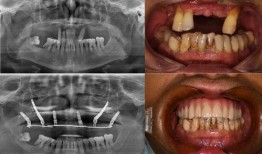

佛山种牙爆料事件视频曝光,揭露行业乱象引发关注

最近佛山那边的种牙事件可是闹得沸沸扬扬的,咱们得好好来聊聊这个话题。你有没有看过那个爆料视频?简直让人瞠目结舌啊!事件回顾:佛山...

2025-11-01 33 -